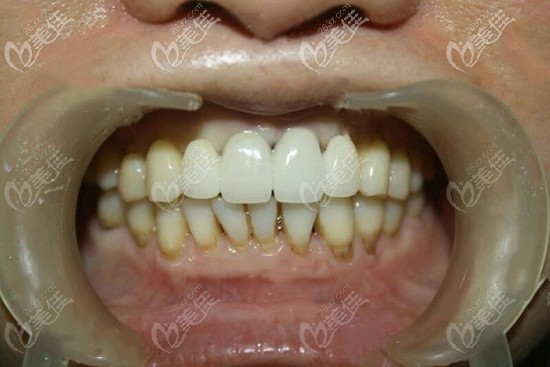

術后照片:

門牙缺失四顆種植案例圖片